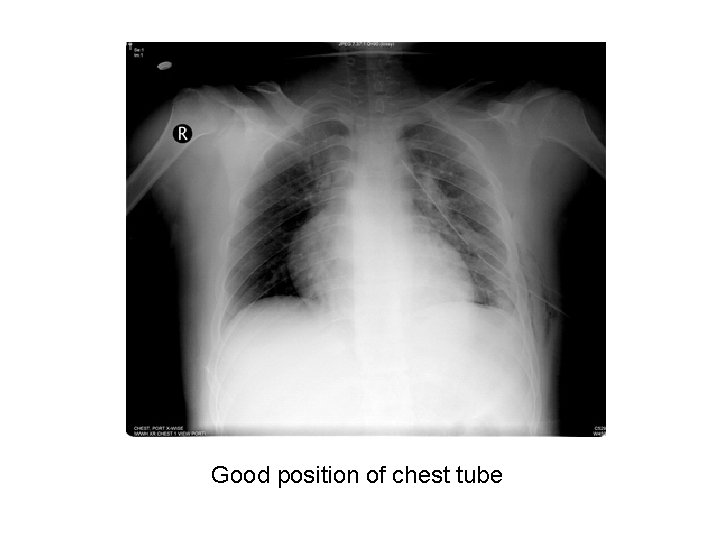

Good position of chest tube